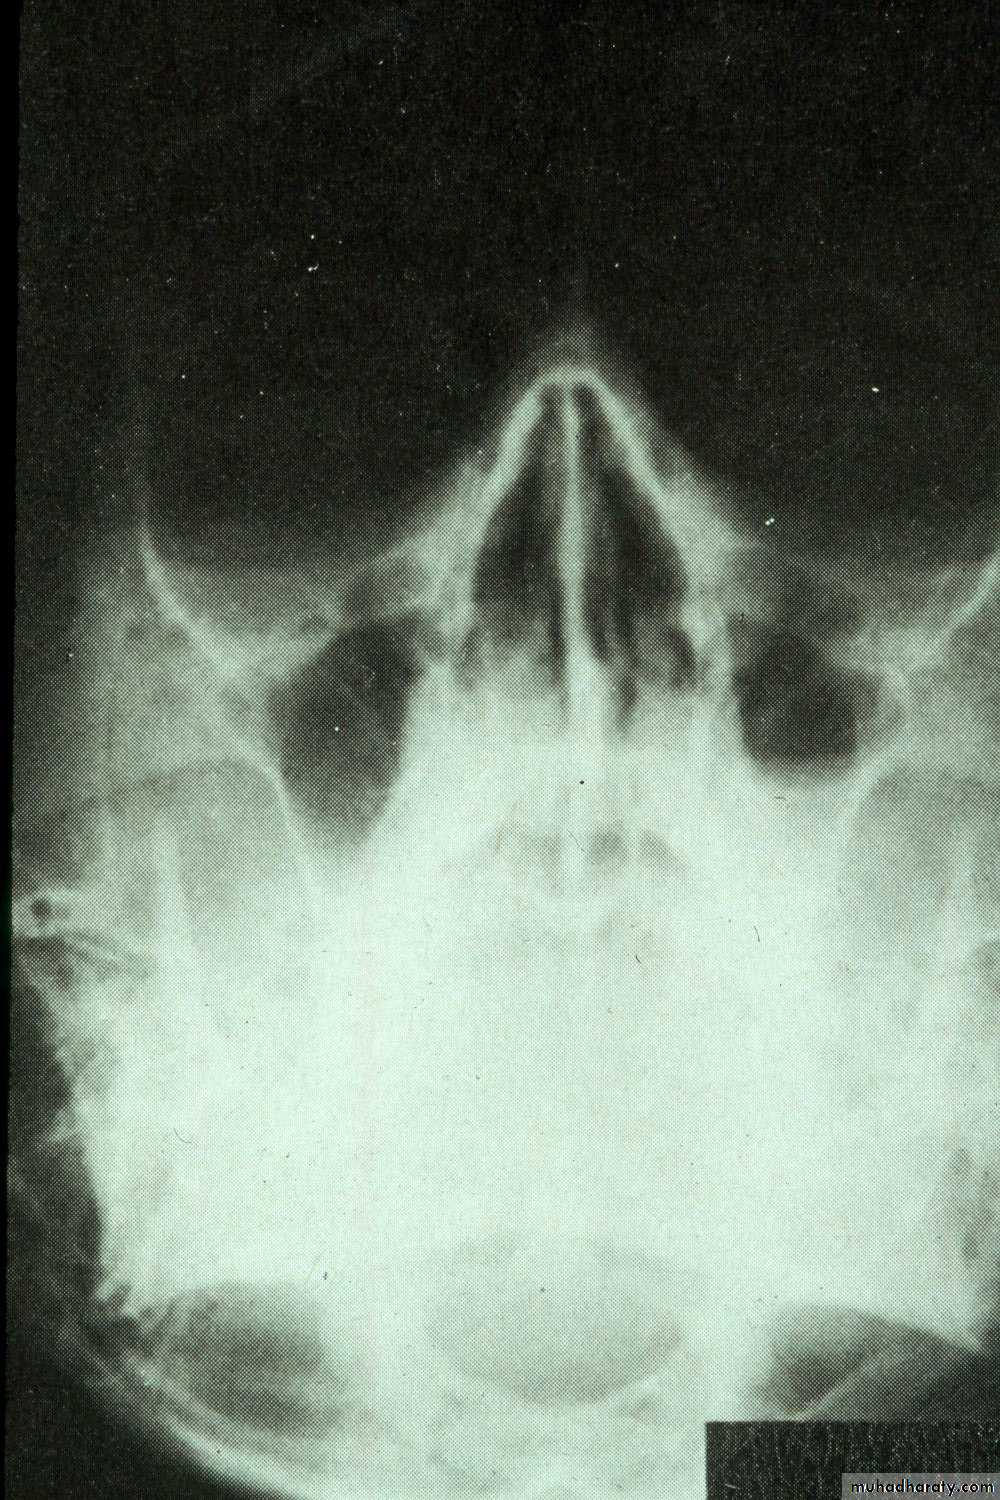

• Extraoral views:• Occipitomental View (15° OM): it’s called Water’s view. The presence of pus will produce a horizontal fluid level in this view; provided that there is air above it. As a measure of confirmation of the diagnosis, the view is repeated with the head tilted toward the side of pathology. The fluid level remains horizontal.

Water’s view with air-fluid level in left maxillary sinus

Water’s view showing air-fluid level in right maxillary sinus and mucosal thickening in left maxillary sinus